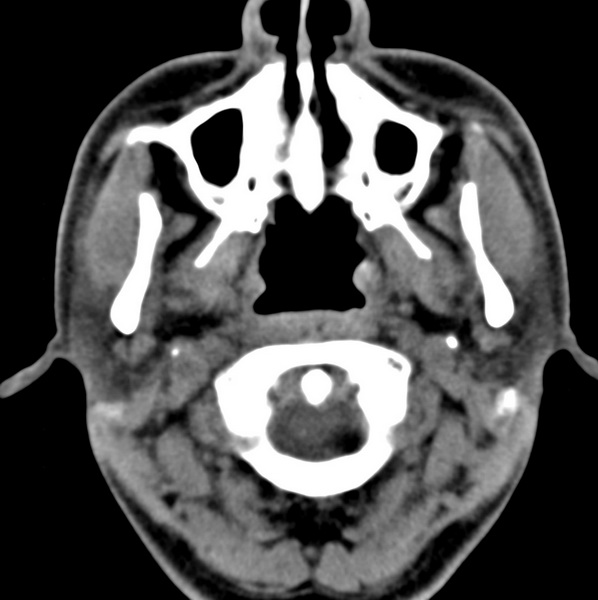

男、31、鼻咽部肿瘤放疗后请帮忙看看。

效果好,右侧破裂孔扩大,局部骨质缺损,为颅底骨质破坏。

1)鼻咽部肿瘤侵犯颅底放疗术后改变。2)左侧蝶窦炎。

咽后壁增厚,左侧咽鼓管隆突增大、咽鼓管咽口变浅,同侧咽旁间隙较窄。右侧颅底骨质破坏?为什么不在同一侧?

鼻咽部肿瘤侵犯颅底放疗术后改变.